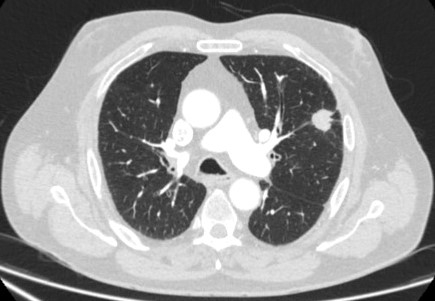

Ground-glass nodules: growth of 2 mm in maximum diameter should be considered potentially significant, while the development of a solid component suggests that further investigation and/or treatment should be considered.[Figure caption and citation for the preceding image starts]: Computed tomography (CT) showing a left upper lobe ground-glass nodule. This was eventually resected 2 years into surveillance because of growth and the histopathology confirmed adenocarcinoma of lung with mixed mucinous-lepidic patternFrom the collection of Dr George Tsaknis, MD, PhD, FRCP(London), MRQA, MAcadMEd, PGCert; used with permission [Citation ends].